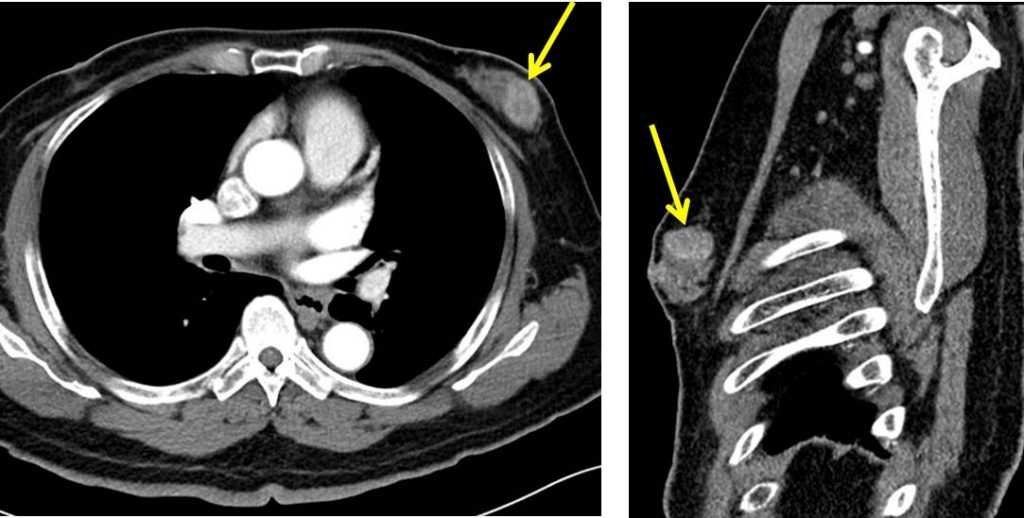

The chest radiologist's role in invasive breast cancer detection Clinical Imaging Male Breast Lump Imaging The majority of male breast lumps are benign and the most common reason is gynecomastia. • symptoms include a lump in the breast, swollen lymph nodes under armpit, nipple changes • treatments include surgery, chemotherapy, radiation therapy, hormone therapy, targeted therapy • involves breast center, breast imaging A partially circumscribed retroareolar mass in a male with suspicious microcalcifications; Most men. Male Breast Lump Imaging.